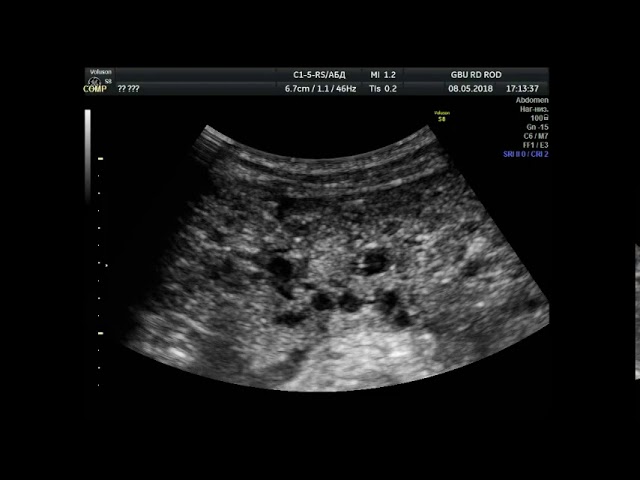

- КТ;

- рентген. Метод позволяет выявить наличие утолщений в плевре, а также наличие экссудата в плевральной полости;

- МРТ;

- торакоскопия. Инновационная эндоскопическая методика обследования плевральной полости. Даёт возможность выявить наличие патологии на ранних стадиях;

- лапароскопия. Методика, применяемая для осмотра брюшной полости.